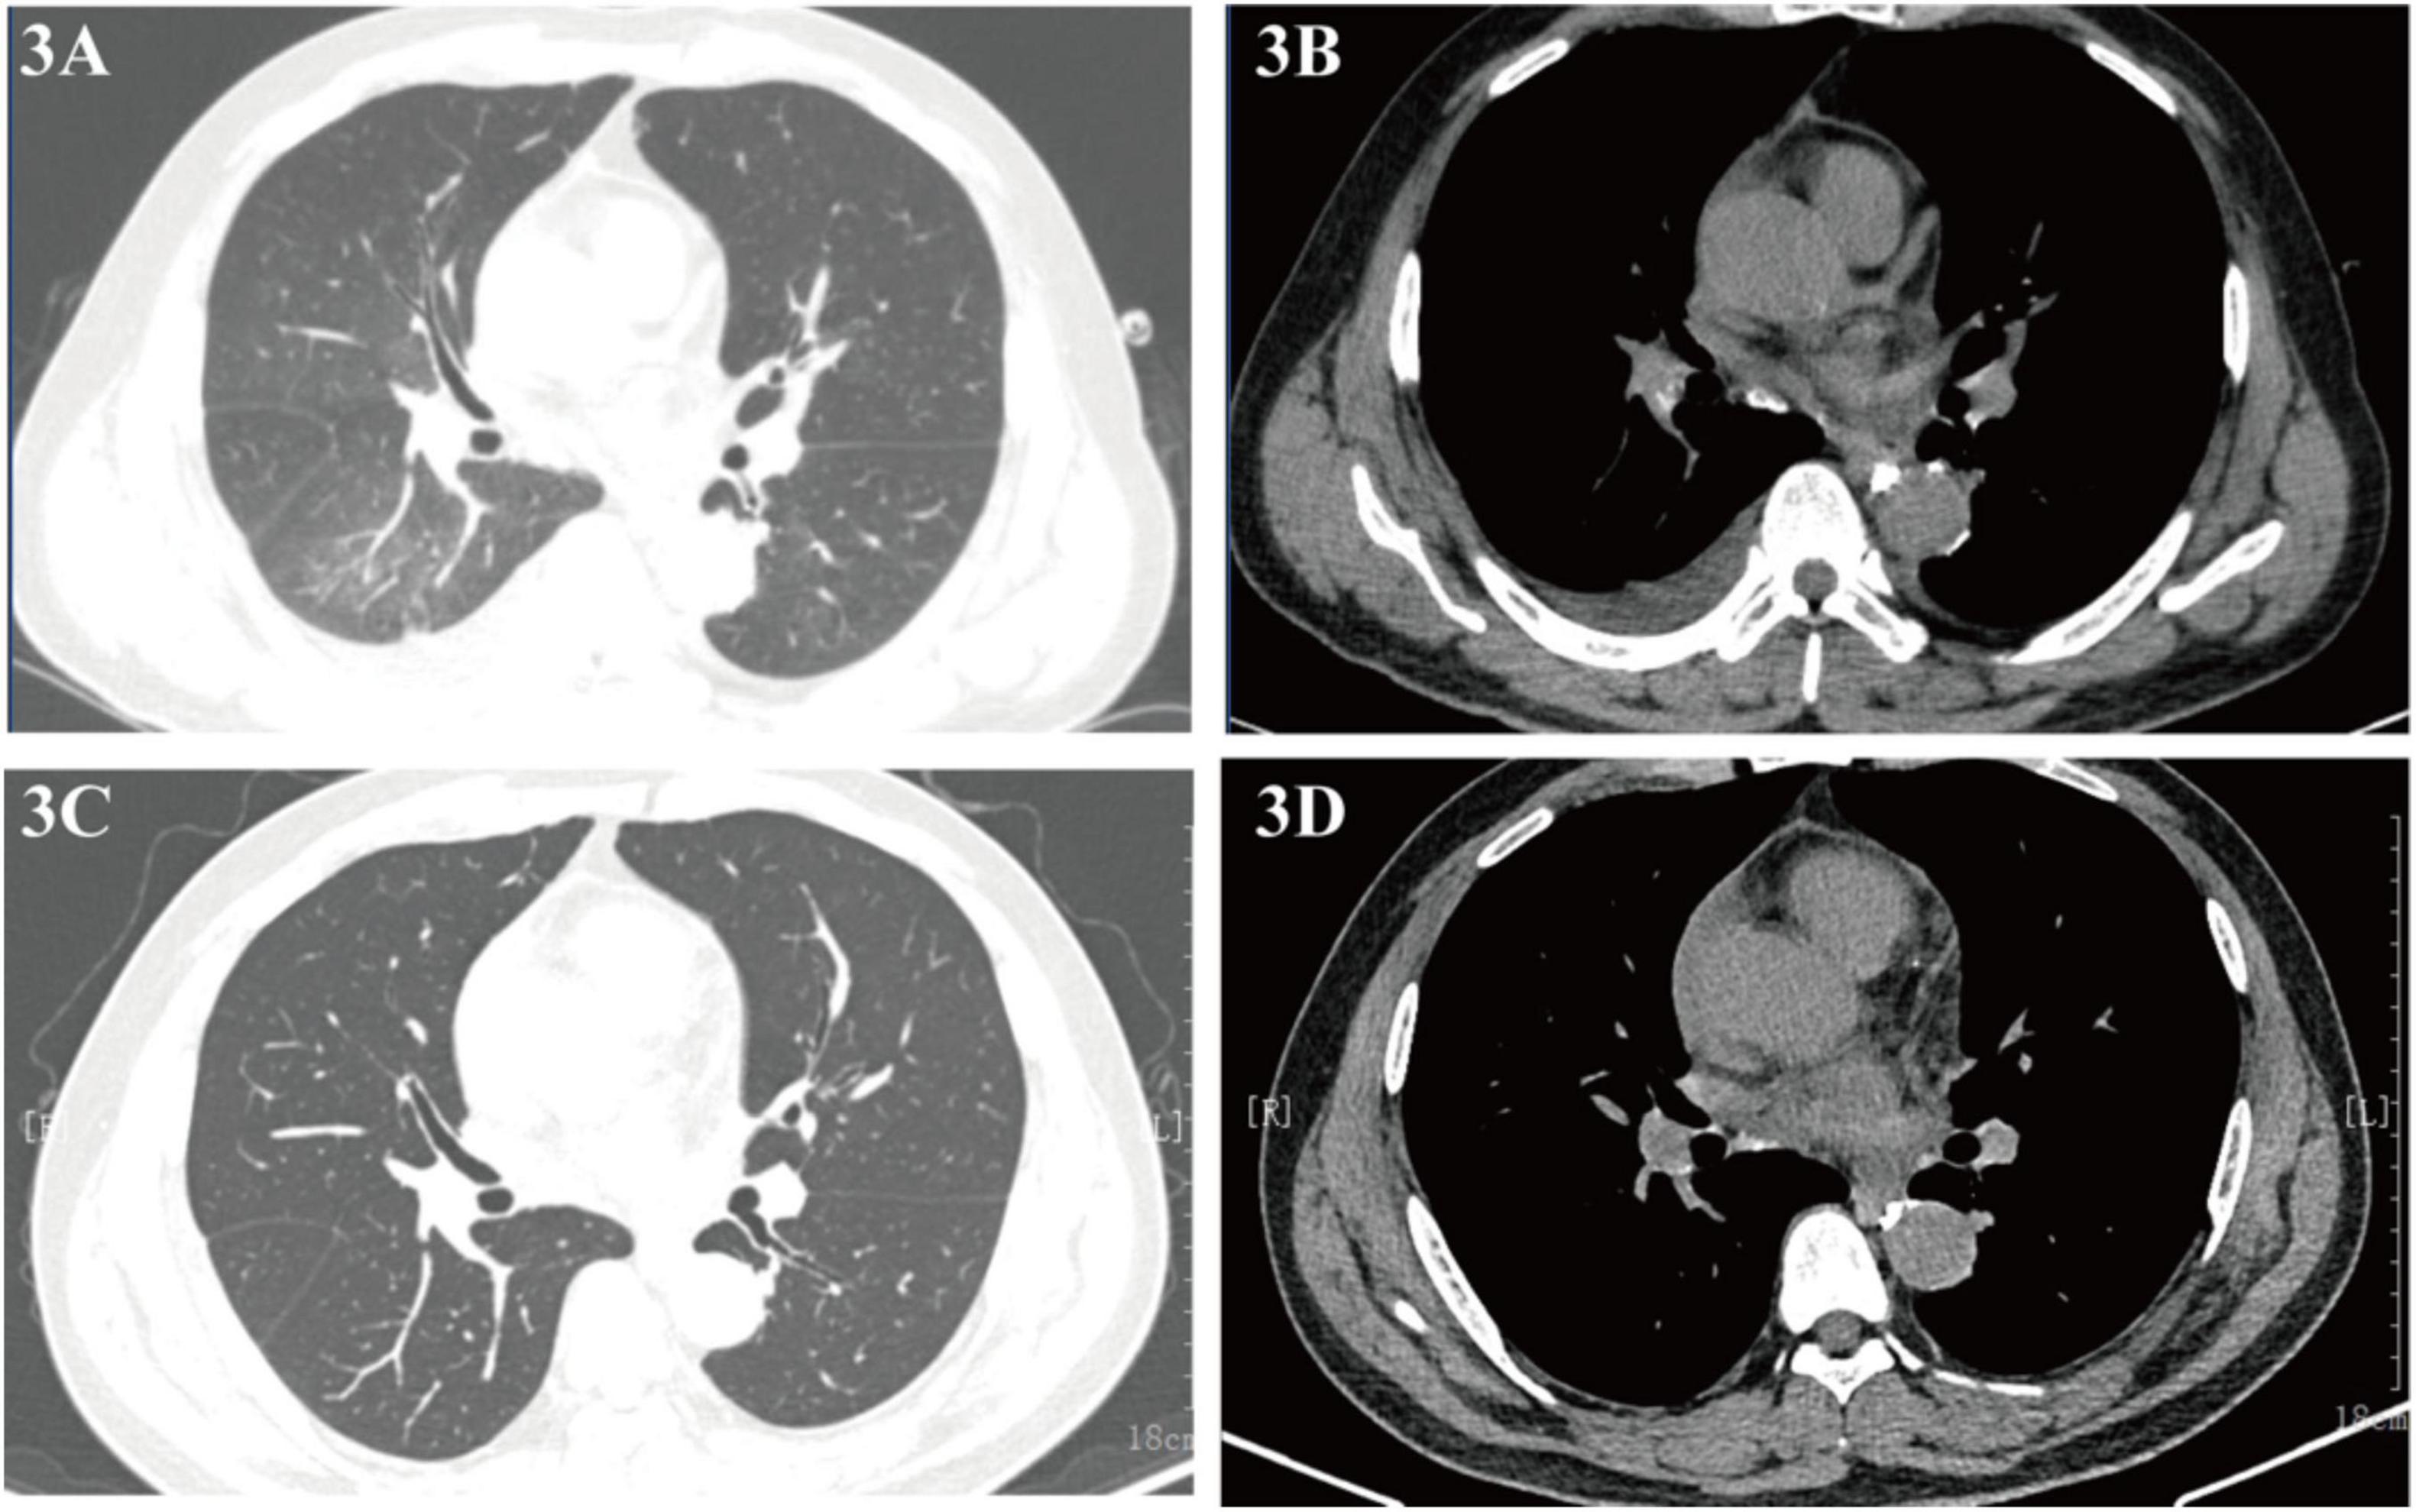

Pulmonary Lymphatic Perfusion Syndrome (PLPS) is a rare condition characterized by abnormal lymphatic drainage into the lungs, leading to symptoms such as chyloptysis and chylous effusions. We report a case of a 54-year-old male with PLPS who presented with persistent cough, milky sputum, and pericardial effusion. Following initial misdiagnosis and ineffective empirical treatment for a presumed pulmonary infection, a definitive diagnosis of PLPS was established.The patient underwent successful percutaneous thoracic duct embolization, resulting in complete resolution of symptoms and imaging findings at follow-up. This case highlights the importance of considering PLPS in patients with unexplained chylous effusions and the efficacy of lymphatic intervention as a treatment option.